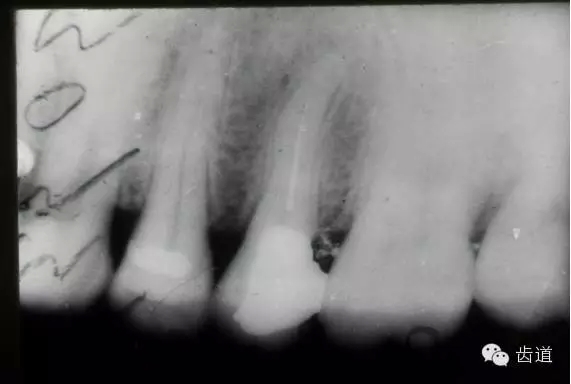

左下7根充后下唇麻木

左下5根管預備后下唇麻木